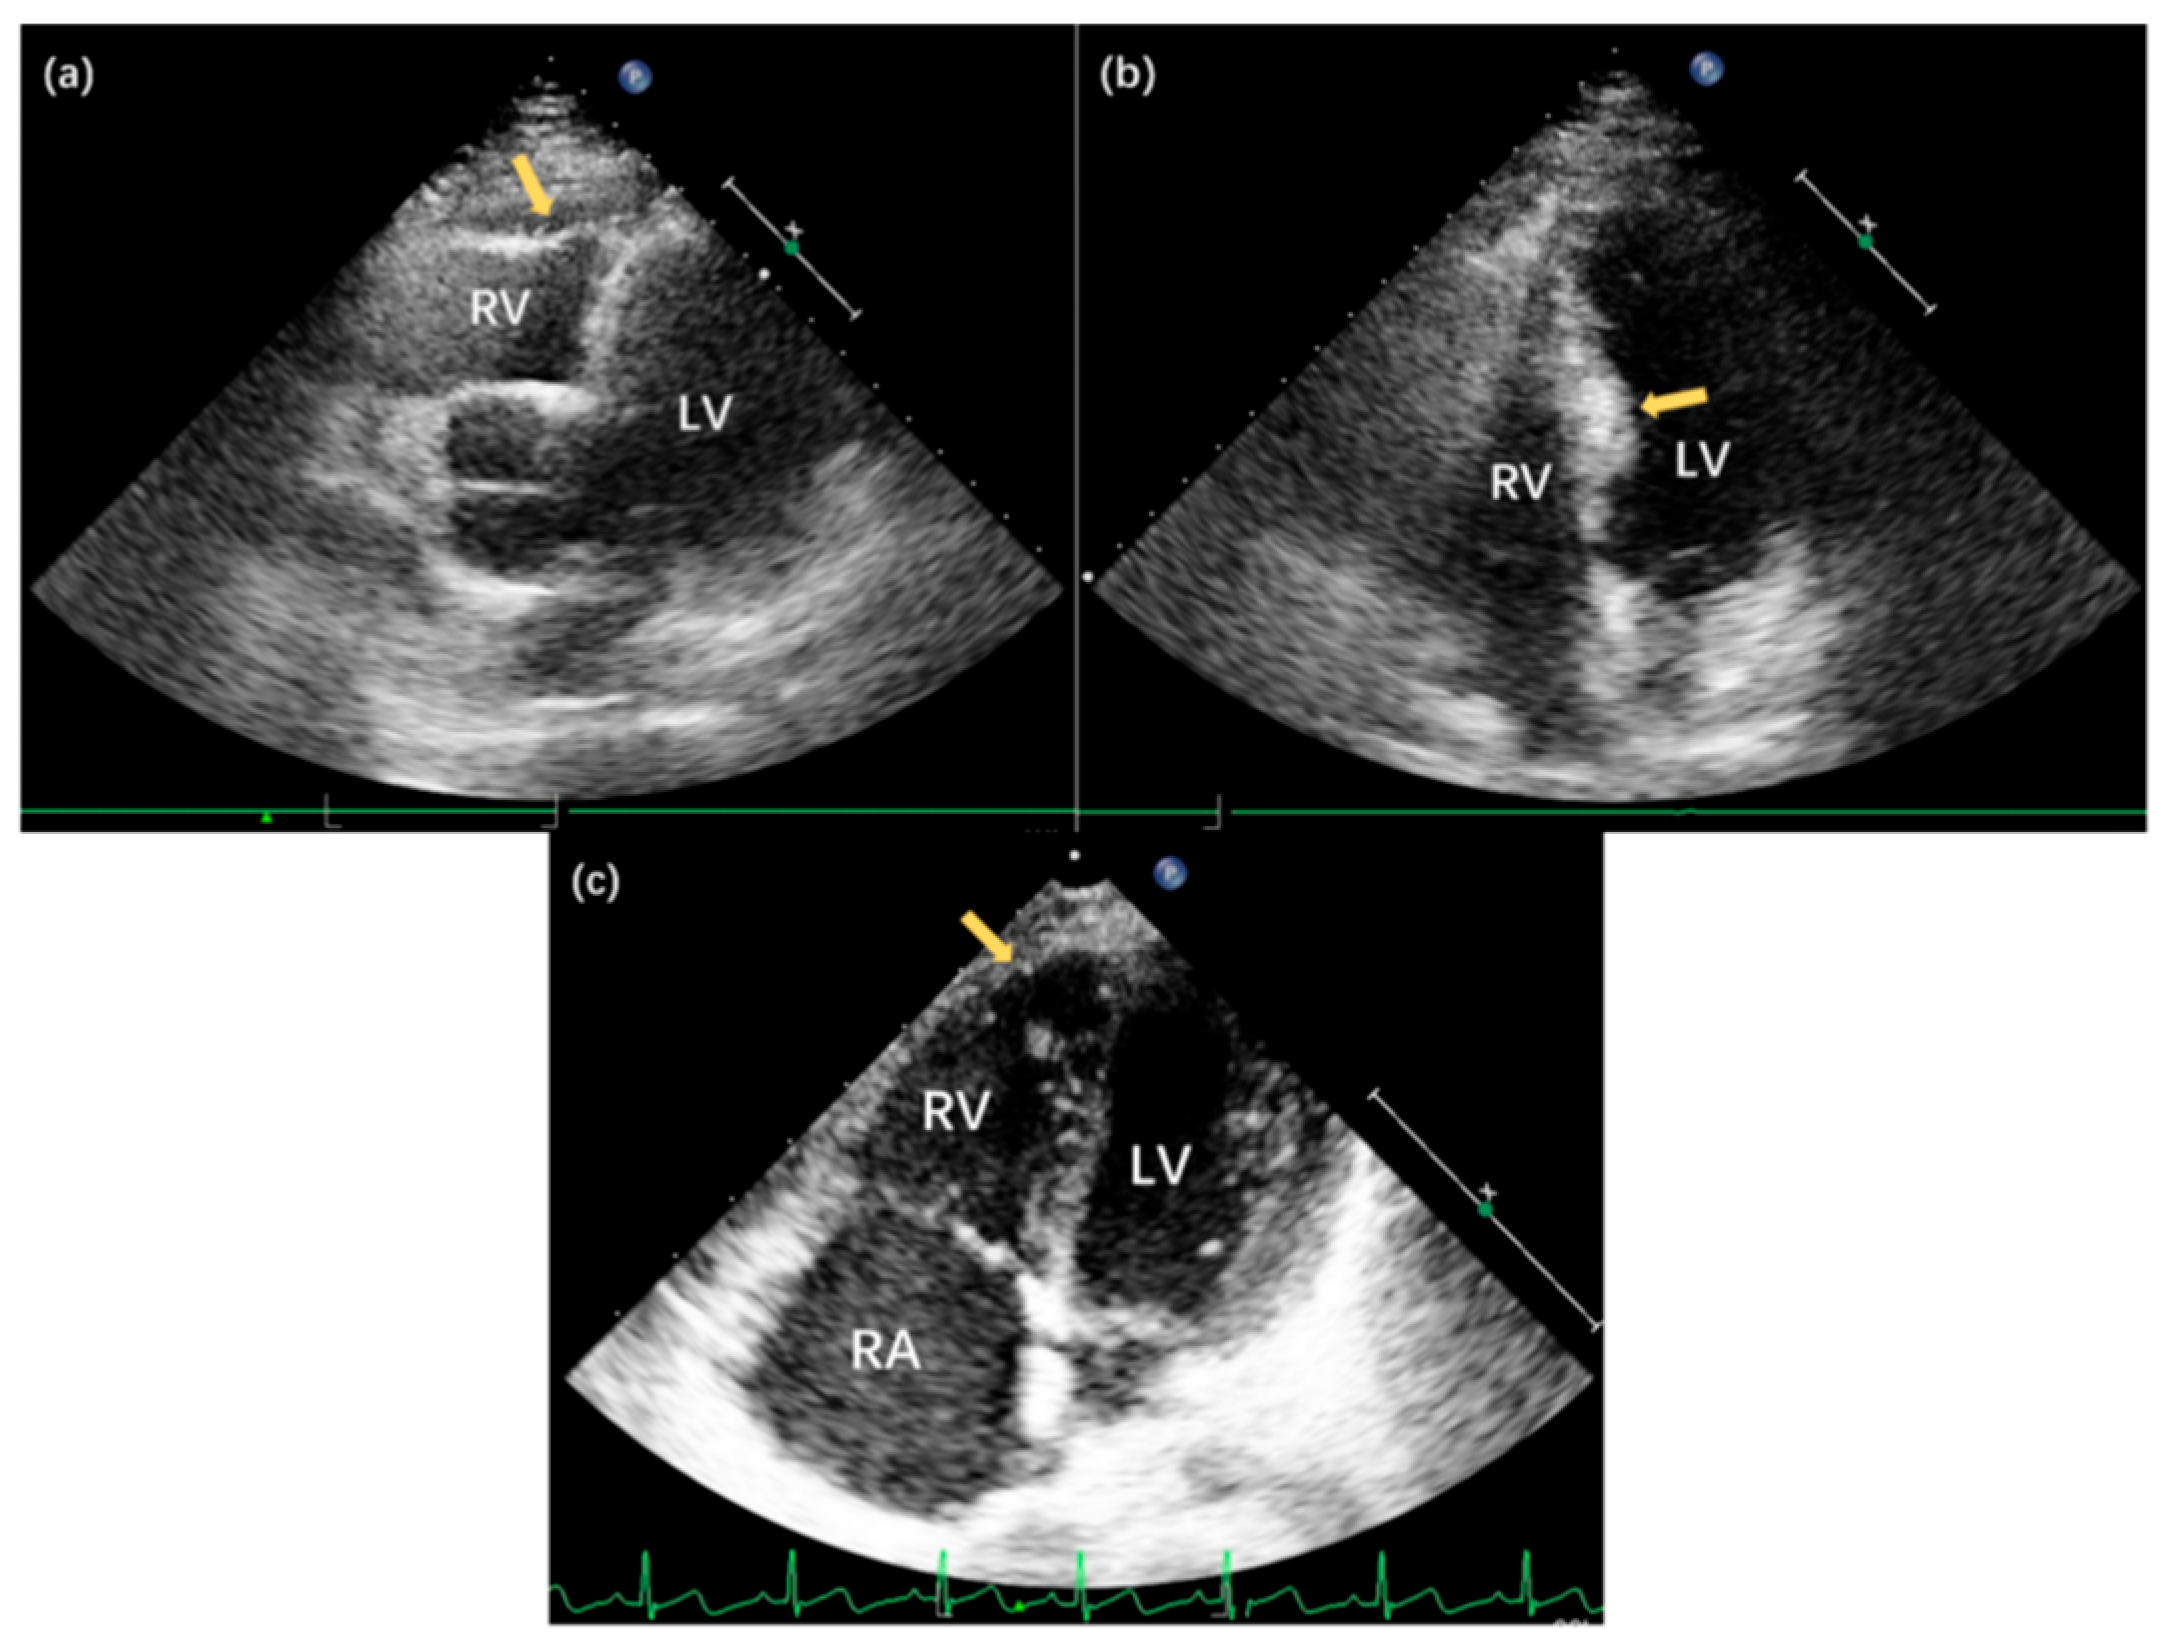

Echocardiography and contrast-enhanced CT revealed prominent outward bulging of the apical RV free wall, accompanied by marked myocardial thinning resembling replacement by fibroelastic tissue. Notably, prominent trabeculations were observed within the aneurysmal regions (Fig. 1b,c). Coronary CT angiography additionally showed a thinner right coronary artery and its branches. The RV appeared dilated and hypokinetic on echocardiography, reflecting significant functional impairment. The Tricuspid Annular Plane Systolic Excursion (TAPSE) was measured at 10.0 mm, and the Fractional Area Change (FAC) was 35%, both consistent with severely reduced RV systolic function. Color Doppler flow imaging demonstrated mild tricuspid regurgitation. Thus, the patient was diagnosed with Uhl’s anomaly, which was first described by Dr. Henry Uhl in 1952, defined by the complete absence of myocardium in the RV free wall [1].

Figure 1: Clinical features of the proband and genetic background of the family with familial Uhl’s anomaly. (a) Electrocardiogram demonstrating sinus arrhythmia in the proband, characterized by irregular P-P intervals; (b) Echocardiographic four-chamber view of the proband revealing apical right ventricular (RV) free wall bulging and thinning (yellow arrow), with near-complete congenital absence of myocardium replaced by fibroelastic tissue. Note the prominent trabeculations in the aneurysmal area (white arrow); (c) Contrast-enhanced computed tomography (CT) of the proband corroborating the apical RV wall bulge and extensive trabeculation (arrow); (d) Pedigree showing an autosomal dominant inheritance pattern. The arrow indicates the proband (III-1). The heterozygous TTN variant co-segregates with all affected family members.

Given the suspected genetic basis of the proband’s cardiac structural abnormalities, all four family members underwent transthoracic echocardiography. The proband’s mother demonstrated no cardiac abnormalities. In contrast, the father and sister exhibited right ventricular structural changes similar to those observed in the proband, although with milder phenotypic expression (Table 1, Fig. 1d and Fig. 2). These findings supported the possibility of a familial form of the disease.

Figure 2: Echocardiographic findings in family members with familial Uhl’s anomaly. (a) Apical five-chamber view of II-2, demonstrating pronounced thinning of the right ventricular (RV) apical wall (arrow) with slight bulging; (b) Apical four-chamber view of II-2, revealing asymmetric septal hypertrophy with a maximal thickness of 13.0 mm in the mid-septal region (arrow); (c) Apical four-chamber view of III-2, showing significant thinning of the RV apical wall (arrow) without substantial bulging, demonstrating the variable expressivity of the congenital anomaly among affected family members.